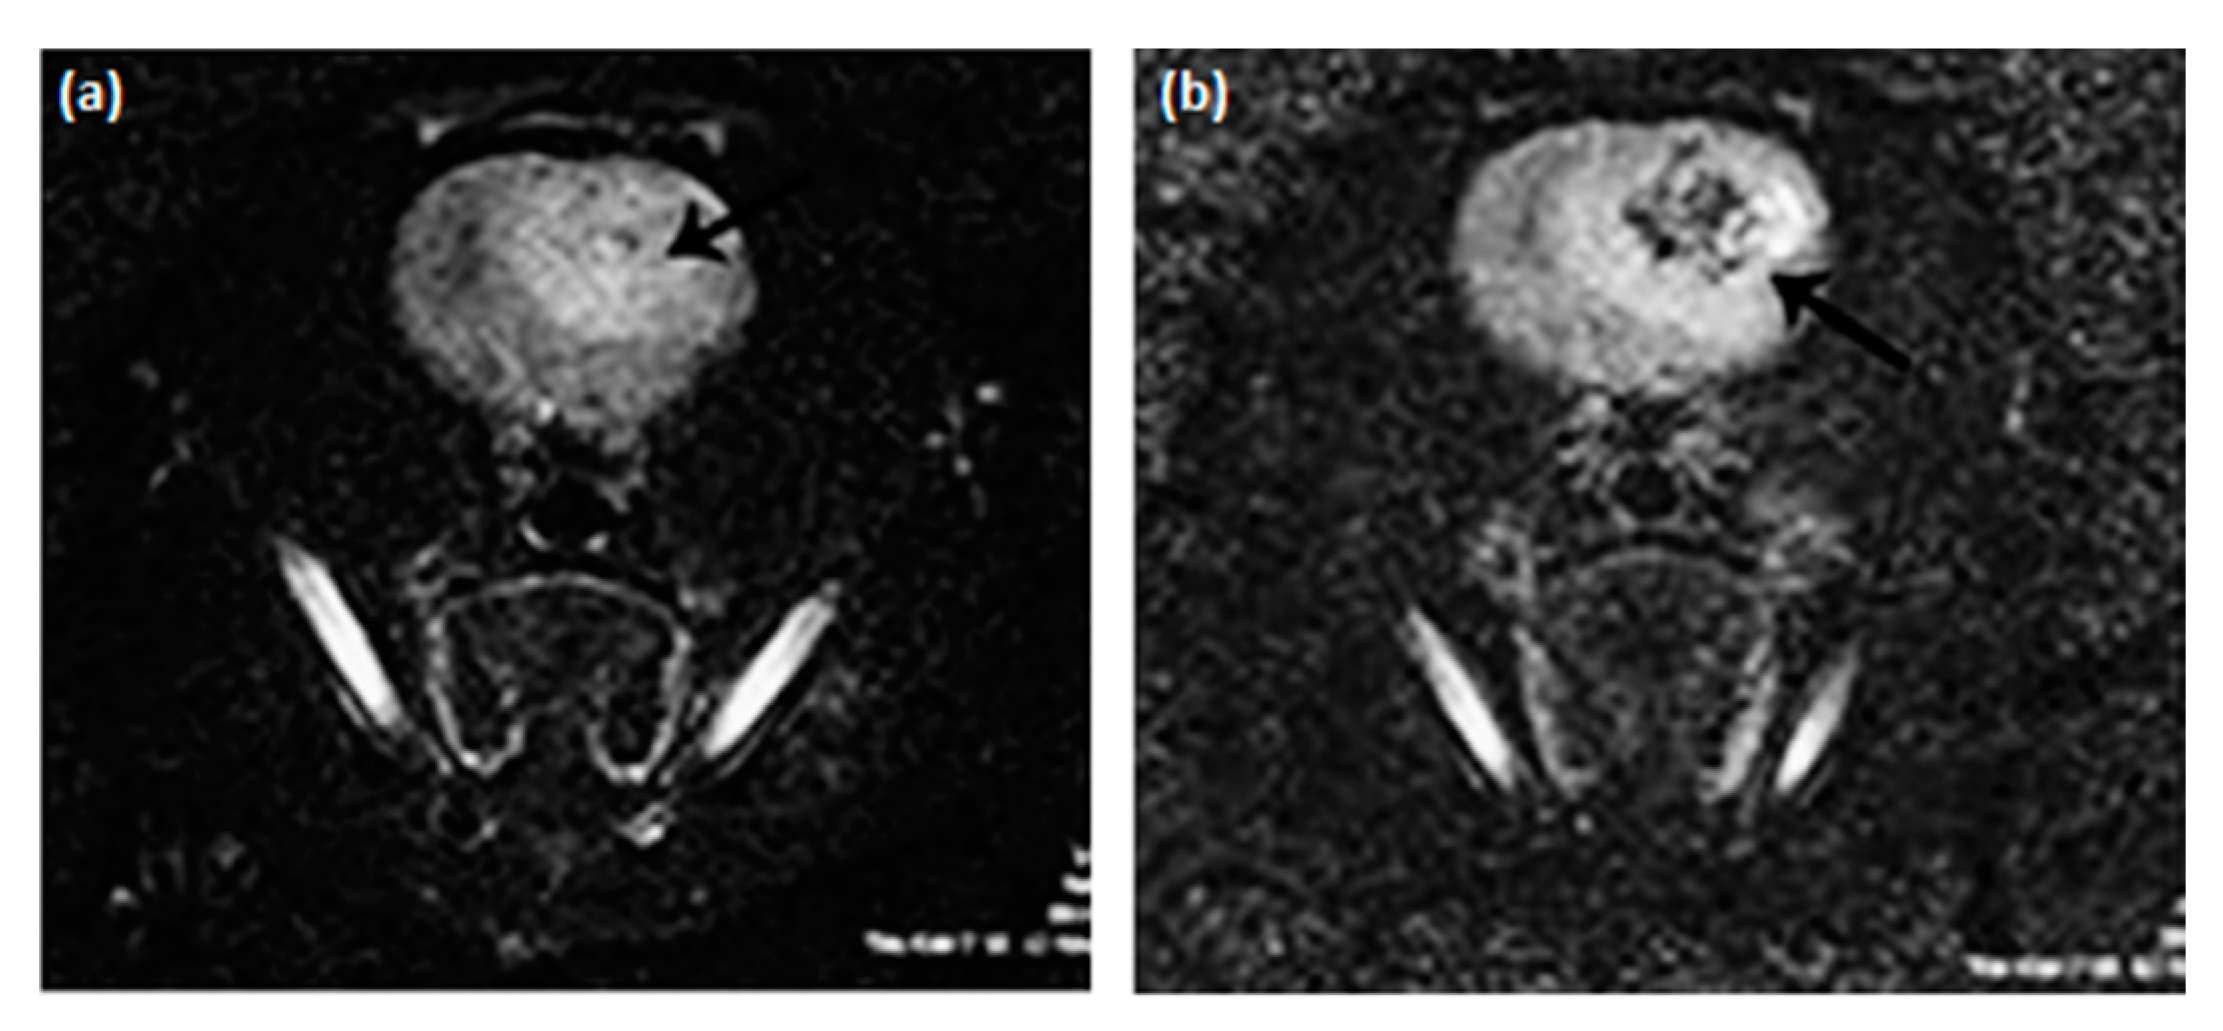

- Hobson, N.J.; Weng, X.; Siow, B.; Veiga, C.; Ashford, M.; Thanh, N.T.; Schätzlein, A.G.; Uchegbu, I.F. Clustering superparamagnetic iron oxide nanoparticles produces organ-targeted high-contrast magnetic resonance images. Nanomedicine 2019, 14, 1135–1152. [Google Scholar] [CrossRef]